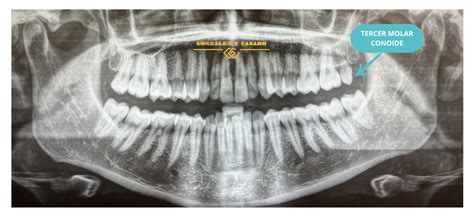

Ejemplo de diente conoide.

- Conoidismo: La corona y la raíz del diente poseen forma conoide. La zona más apical e incisal son las que acaban en punta.

- Conoidismo: Además de verse afectada toda la pieza, también puede aparecer la forma de cono sólo en la corona del diente.

Concretamente, en este post queremos hablarte de los dientes cónicos. ¿Sabes qué son, por qué aparecen y cómo se pueden corregir? Como su nombre indica, los dientes cónicos o conoides son aquellos que tienen forma de cono, con un tamaño reducido en comparación con los demás. Es verdad que no es una situación común y que afecta a un porcentaje de la población muy bajo, pero puede aparecer algunos casos. A pesar de no ser una alteración que no implica un riesgo para la salud bucodental, sí que puede suponer un problema estético y, por ende, de confianza en uno mismo.